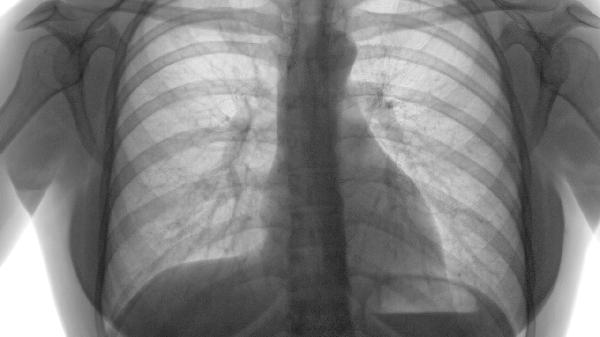

在康复治疗师指导下进行腹式呼吸训练,提升肺功能储备。使用呼吸训练器改善通气效率,当出现戒烟后咳嗽加重时,可通过雾化吸入生理盐水保持气道湿润。

肺气肿患者日常需保持环境空气流通,避免接触二手烟。饮食选择高蛋白、高维生素的银耳羹、百合粥等润肺食物,每周进行3次30分钟以上的快走或游泳锻炼。定期进行肺功能检测,当出现急性加重症状如咳黄脓痰、静息气促时需立即就医。